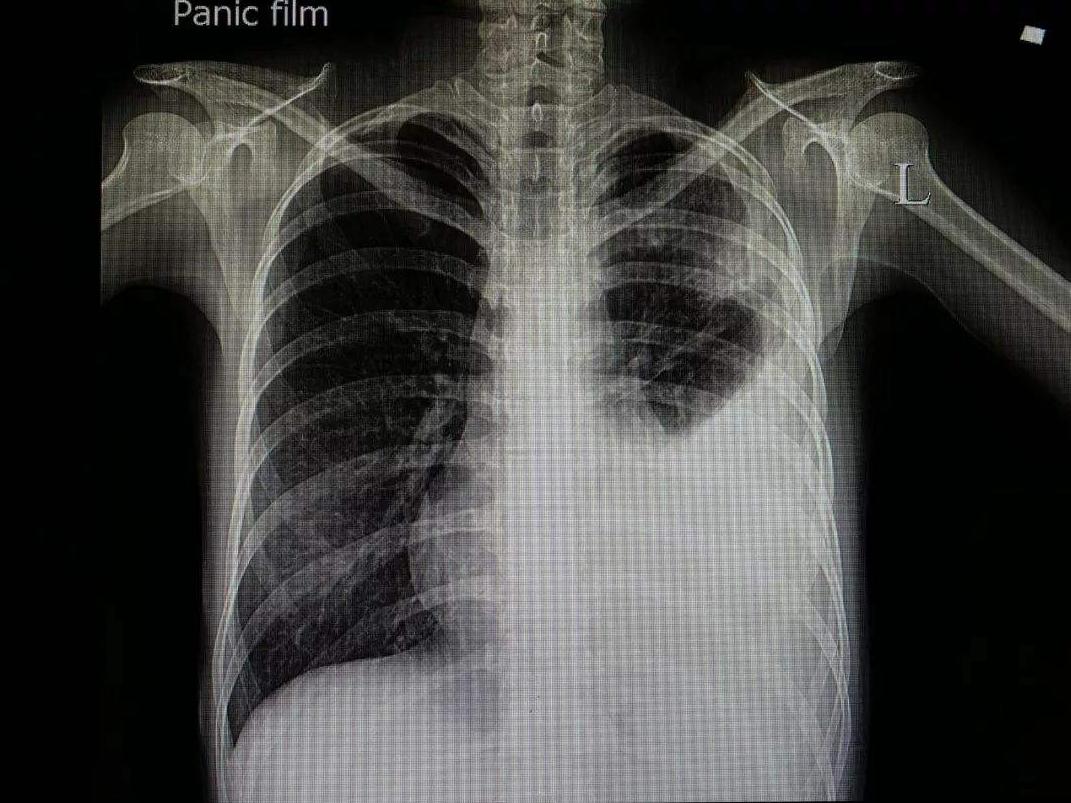

少量积液时肋膈角变钝;中等量积液,肺野中下部呈均匀致密影,呈上缘外高内低的凹陷影;大量积液患侧全呈致密影,纵隔向健侧移位。肺下积液出现膈升高假象,侧卧位或水平卧位投照可确定。叶间包裹积液时在胸膜腔或叶间不同部位,有近似圆形、椭圆形的阴影,侧位片可确定部位。